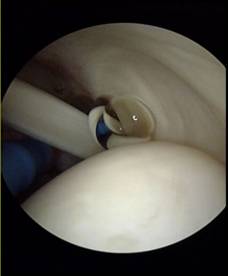

Zunehmend wird dieser Eingriff nun arthroskopisch - also durch "Schlüsselllochchirurgie" mit speziellen Instrumenten durchgeführt. Diese Operationstechnik verlangt große Erfahrung vom Operateur. Dabei setzt sich zunehmend die sogenannte doppelreihige Rekonstruktion mit überbrückenden Nähten zwecks Refixation der Sehne am Knochen durch, da diese einen hohen Anpress- und Flächendruck bietet (Double row - bridging suture, footprint reconstruction):